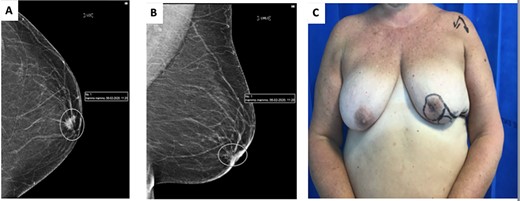

(A) cranio-caudal view (CC) mammogram showing speculated retroareolar mass. (B) Latero-medial oblique (LMO) view mammogram showing speculated retroareolar mass. (C) Preoperative image of left breast, note retracted nipple.

A 62-year-old woman underwent routine screening bilateral mammogram which revealed the presence of a spiculated density behind the left NAC (Fig. 1A and B). On clinical examination the left nipple appeared retracted and indurated (Fig. 1C). An ultrasound assessment detected a 12-mm irregular mass corresponding to the mammographic abnormality with an abnormal lymph node in the ipsilateral axilla. Core biopsies confirmed the presence of a grade 2 invasive ductal carcinoma ER8 PR8 Her2 negative, metastasized to the axilla. Staging CT scan confirmed no evidence of distant metastatic disease. MDT decision was made to proceed to offer mastectomy or central excision with either primary closure or local flap reconstruction and axillary clearance. Following informed consent, a central quadrantectomy and a Grisotti flap were undertaken.